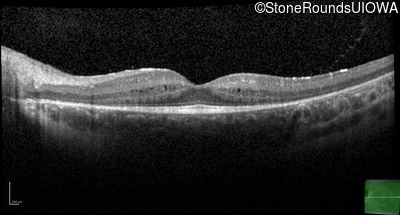

Age at visit: 10 years